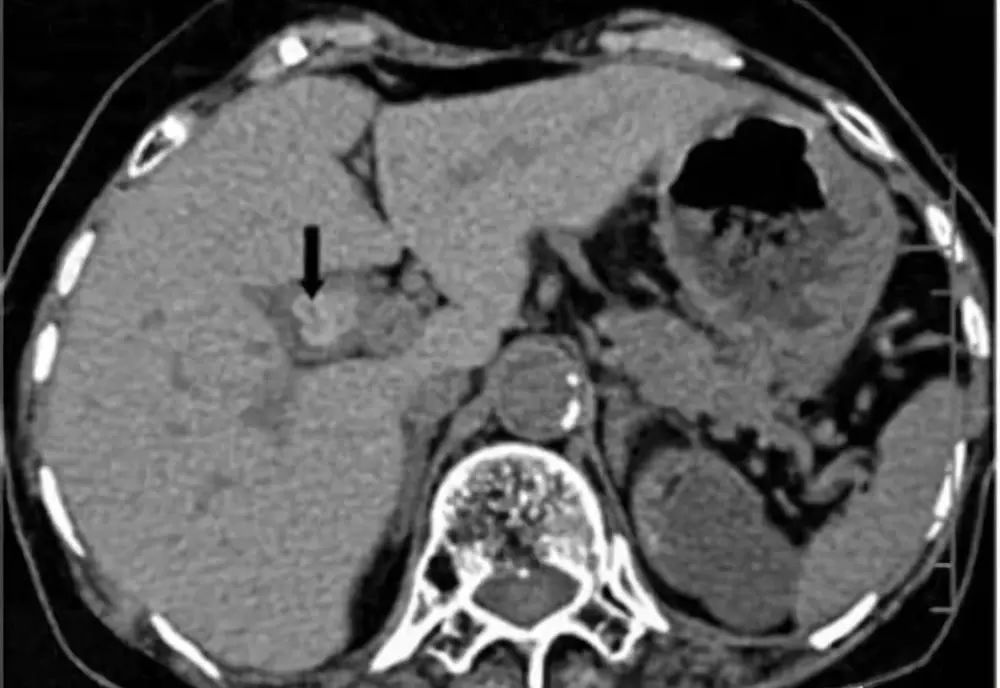

胆囊息肉是胆囊壁向腔内呈息肉样突起的一类病变的总称,包括肿瘤性息肉和非肿瘤性息肉,一般症状轻微,甚至无症状。目前胆囊息肉的病因尚不清楚,长期饮酒,高脂饮食,不吃早餐、压力大、熬夜及生活不规律者,容易得胆囊息肉。胆囊息肉以良性息肉更为多见,但也要预防癌变。

一旦发现就要定期复查,如果符合以下手术指征,建议尽早手术治疗。如胆囊单发息肉直径超过1厘米以上,蒂粗大者,尤其是基底宽,位于胆囊颈部,年龄超过50岁;胆囊多发息肉合并胆囊结石且有症状;胆囊息肉直径小于5毫米,无症状,要每3~6个月随访,迅速增大或症状明显等。